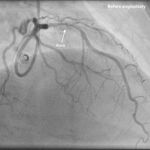

Impella Protected Rotablation PCI

A high-risk PCI performed with Impella support and rotablation for optimal safety and outcomes.